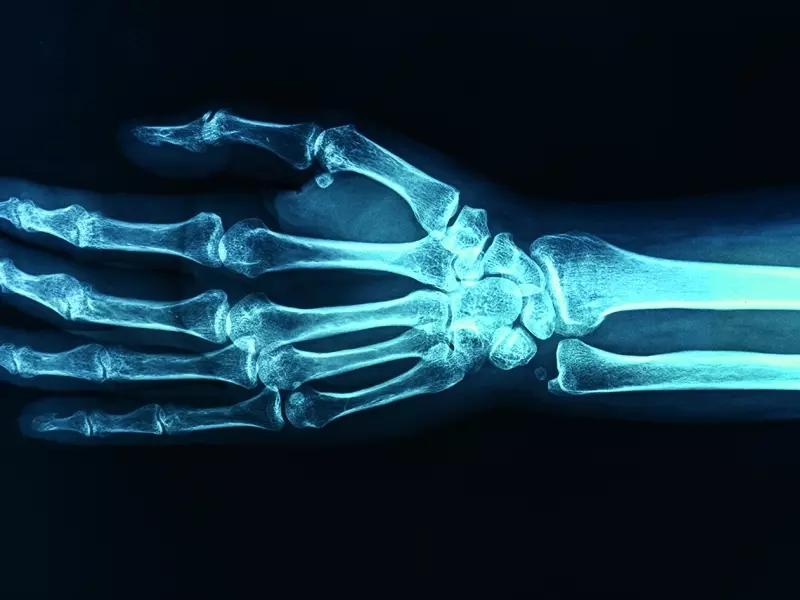

Moment, w którym pacjent zgłasza ból lub parestezje palców 1.–3., kieruje uwagę terapeuty w stronę zespołu cieśni nadgarstka. W ujęciu ortopedycznym struktury anatomiczne wewnątrz i wokół kanału nadgarstka, tj. więzadło poprzeczne nadgarstka – nazwane także troczkiem zginaczy – i pochewki ścięgien mięśni zginaczy przechodzących przez kanał, są opisywane od prawie stu lat jako kluczowe jednostki w tym schorzeniu. W podręcznikach ortopedycznych etiologia cieśni przypisywana jest lokalnej kompresji na nerw pośrodkowy spowodowany bliżej nieokreślonymi restrykcjami lub sklejeniami łącznotkankowymi. I choć zdarza się, że faktyczny problem leży w obrębie tych struktur – zwłaszcza gdy dochodzi do powstania lokalnego obrzęku bądź podwichnięcia kości księżycowatej mających wpływ na ograniczenie przestrzeni oraz wzrost ciśnienia wewnątrz kanału – to częściej problem dotyczy złożonych zaburzeń na przebiegu całego nerwu pośrodkowego. Może to nastąpić zarówno w obszarze przedramienia, jak i w segmentach położonych wyżej. Nadgarstek jest często miejscem manifestującym objawy, co nie znaczy, że wyłącznie on wymaga terapii. W celu ustalenia miejsca dysfunkcji należy wykonać bardzo dokładną diagnostykę różnicową. Czasami w ramach diagnostyki trzeba poddać terapii manualnej kilka miejsc, w których najczęściej dochodzi do kolizji tkanek otaczających nerw pośrodkowy.

Klasycznymi objawami zespołu cieśni nadgarstka są parestezje, bóle stawów nadgarstka i dłoni pojawiające się zarówno podczas ruchu, jak i w spoczynku – szczególnie w nocy. W miarę rozwoju choroby postępuje zanik mięśni kłębu, uniemożliwiając ruch przeciwstawiania kciuka. Następuje wtedy osłabienie chwytu i brak możliwości zaciśnięcia ręki w pięść oraz brak precyzji czy wypadanie przedmiotów trzymanych w ręku, co skłania do wizyty w gabinecie lekarskim. Na podstawie opisanych objawów bierze się pod uwagę operację odbarczania kanału nadgarstka.